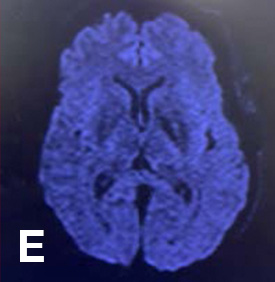

海綿静脈洞部巨大動脈瘤に対しCAS抜去後にhigh flow bypass+内頸動脈近位遮断を行なった症例

左内頸動脈海綿静脈洞部の巨大動脈瘤の患者様です。他院で血管内治療を行なった際に解離が起き、内頸動脈から総頸動脈にステントが留置されており、当院での治療を希望され来院されました。浅側頭動脈ー中大脳動脈バイパスを行なった後、頸部で内膜剥離術を行いstentを抜去し外頸動脈から中大脳動脈にバイパスを作成し、内頸動脈近位部で結紮遮断しています。CAS後でエフィエントを休薬せずに開頭手術を行ったため止血操作に時間を要しましたが合併症なく自宅退院されています。

- D: high flow bypassとSTA-bypass後に内頸動脈を遮断しています。

- E: 術後一過性に静脈還流障害を認めましたが回復しております。